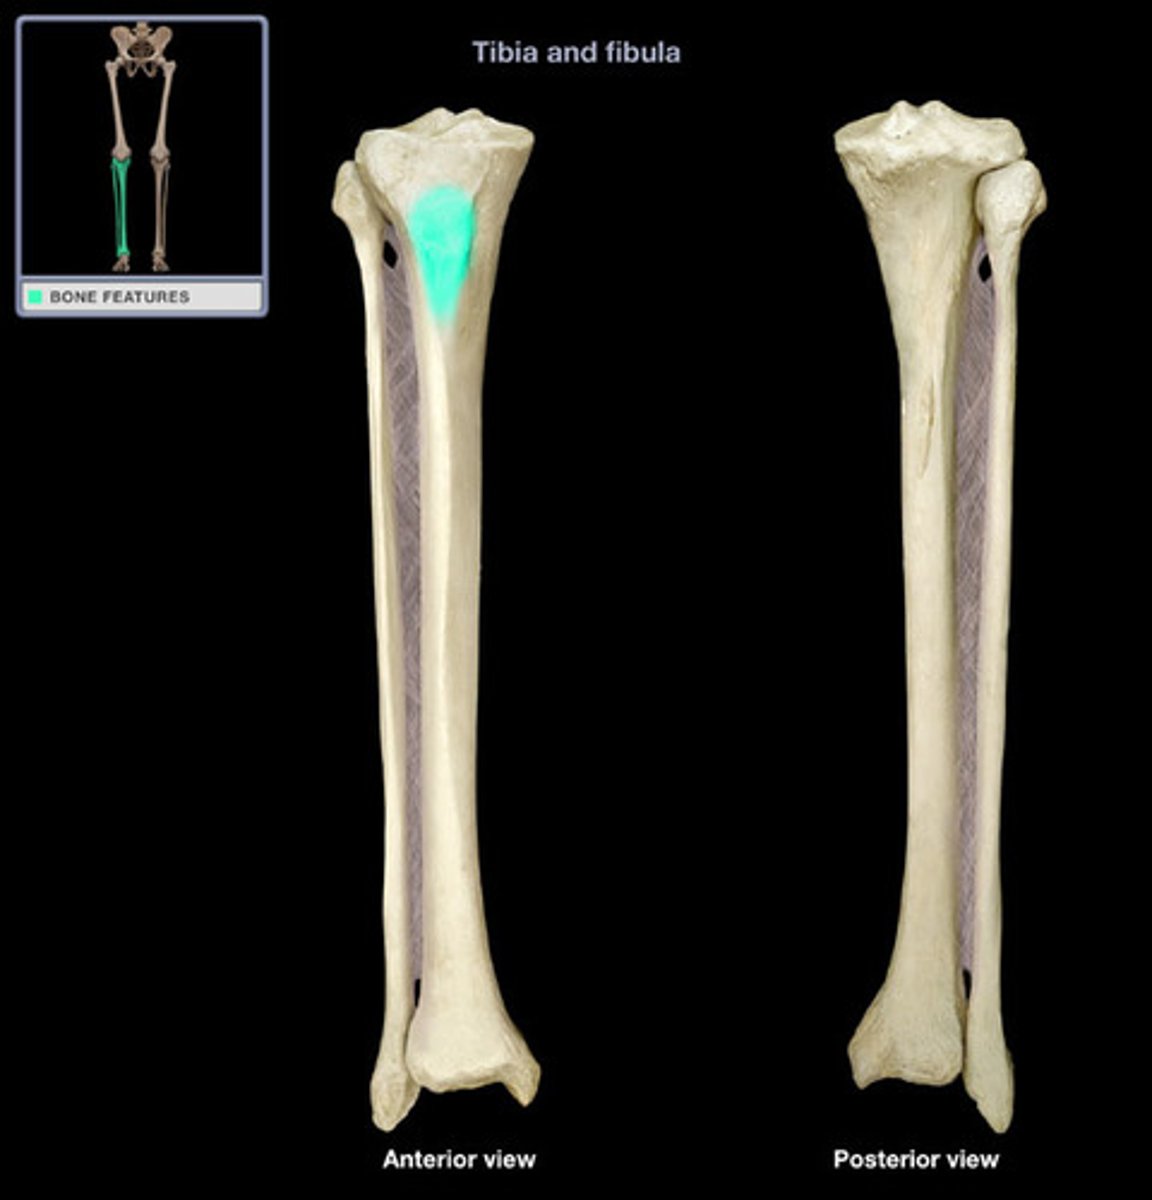

Tibial tuberosity

Semimembranosus sulcus

Gerdy's tubercle (anterolateral tubercle)